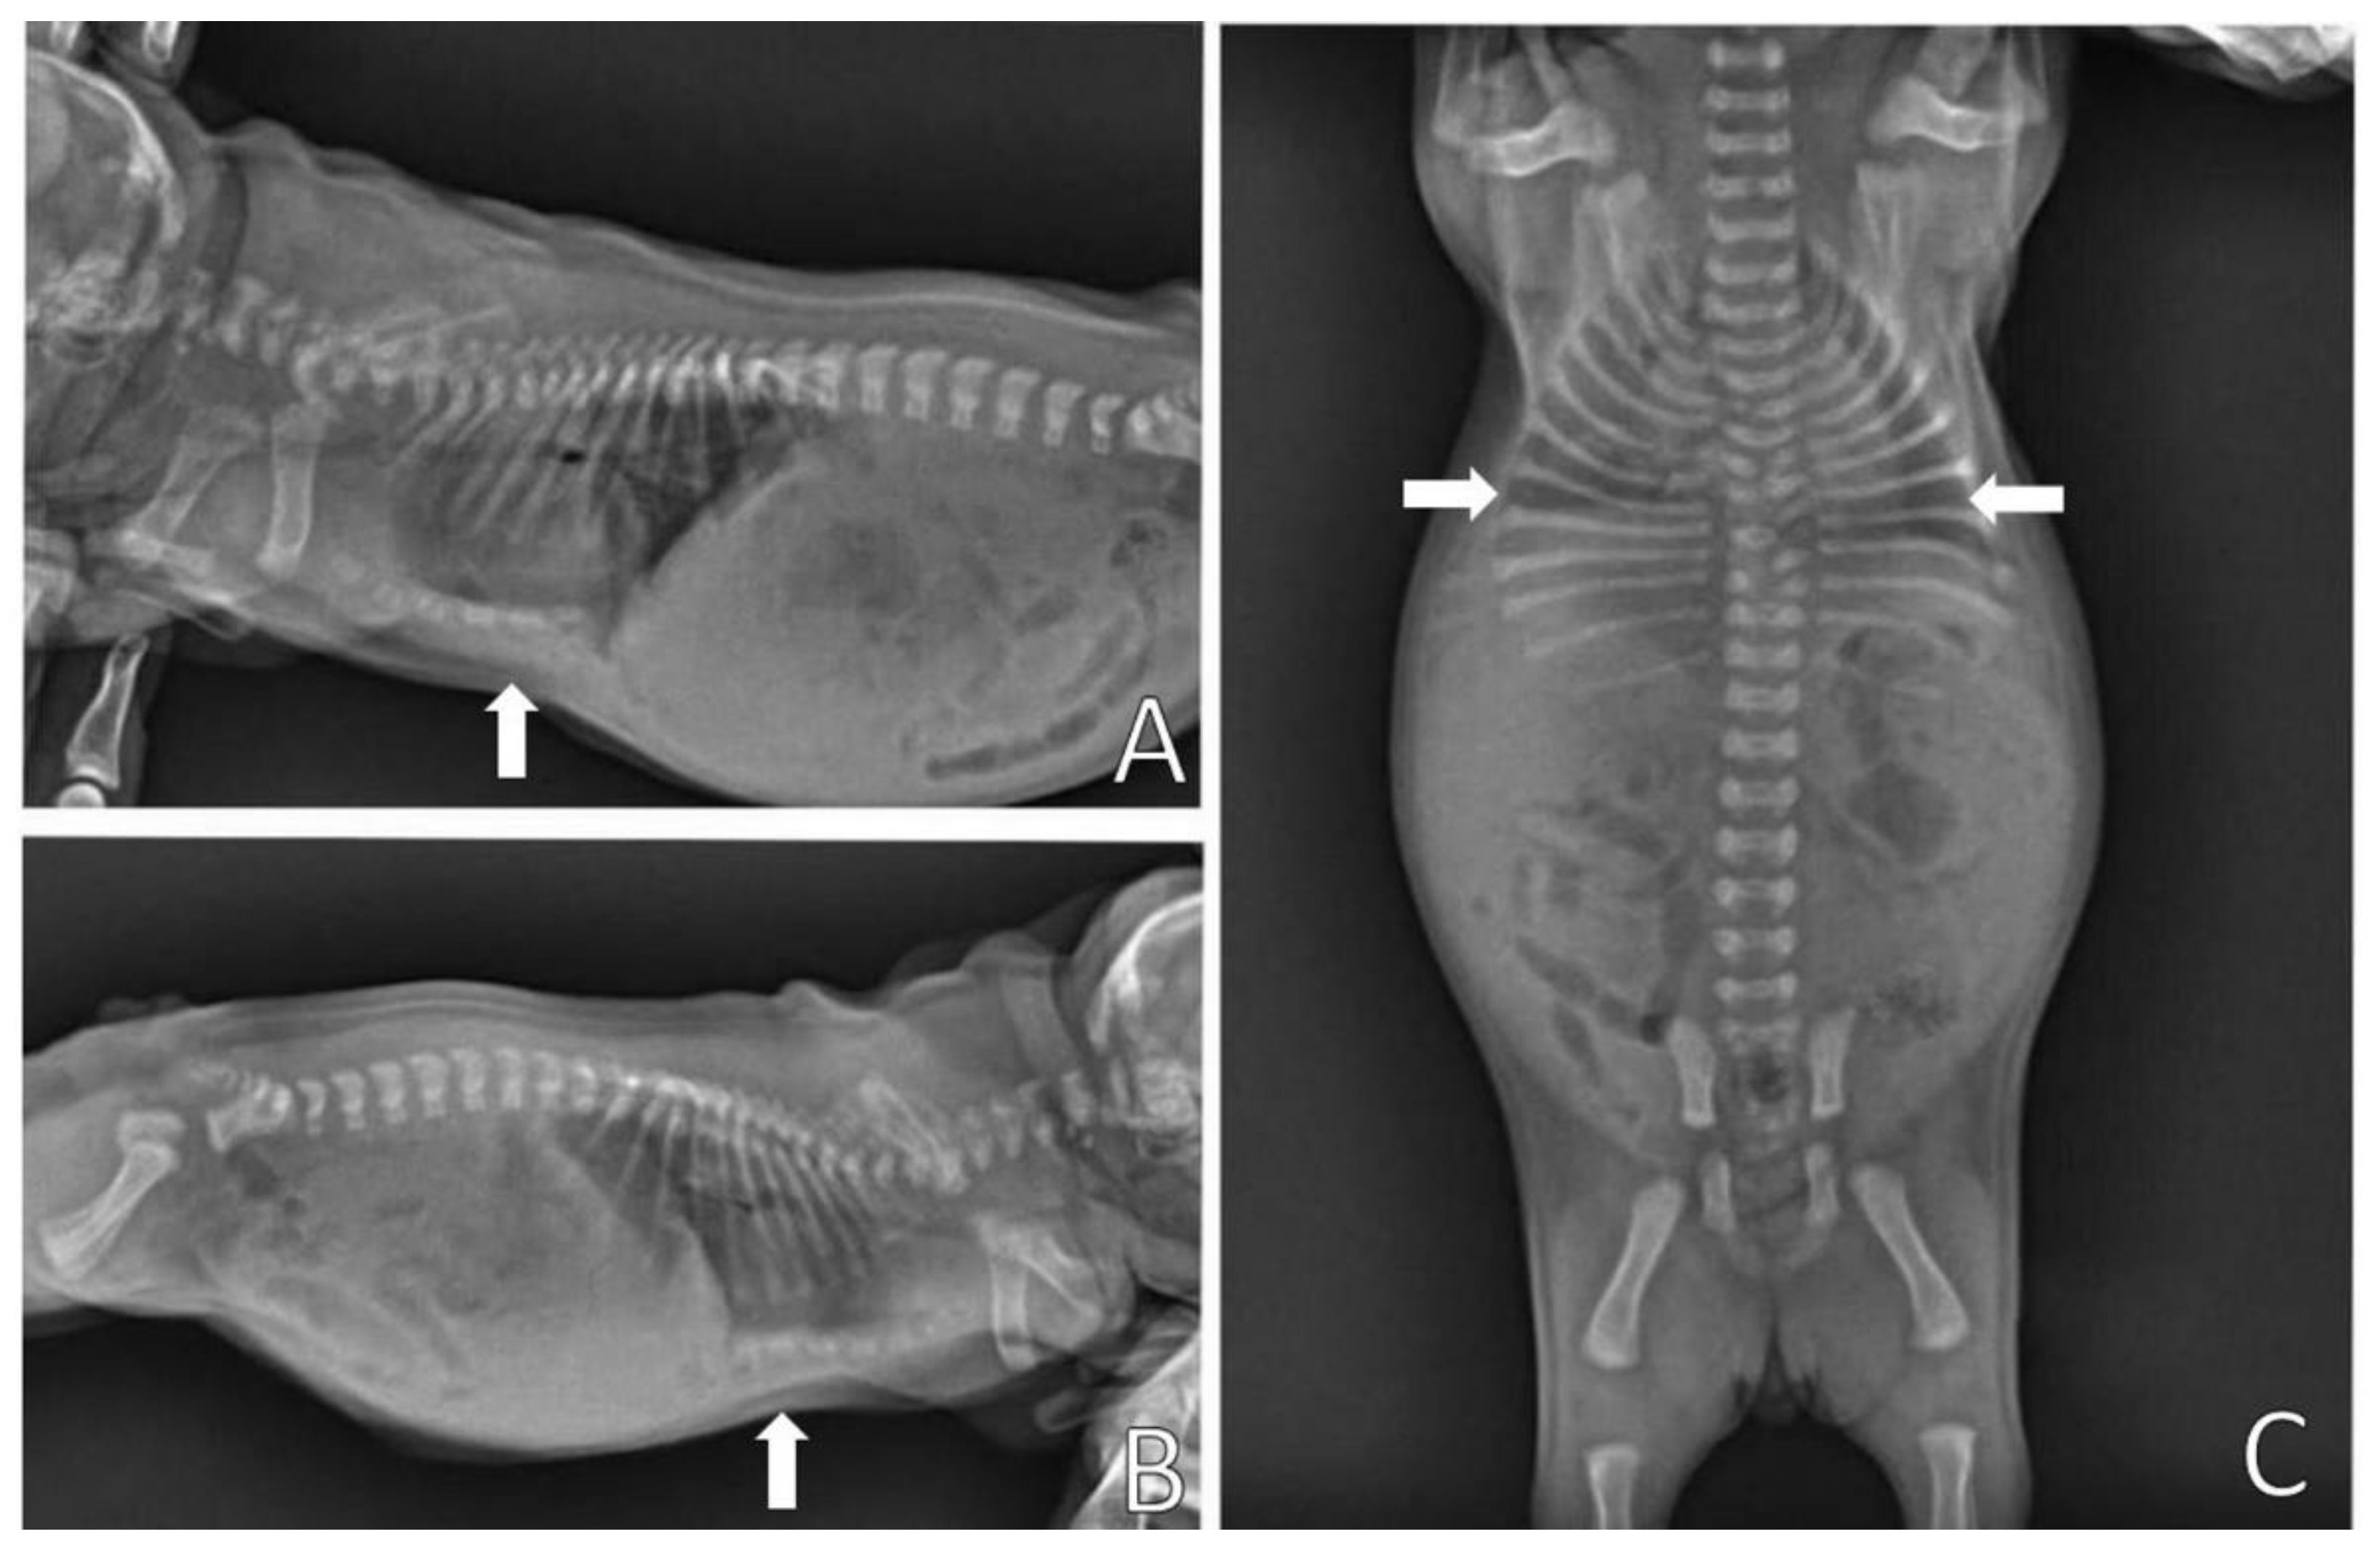

On physical examination, the patient presented dyspnea, substernal retraction during inspiration (Video S3), cyanosis during manipulation, HR 255 bpm, FR 30 mpm, body temperature 36.8 °C, glycemia 151 mg/dL, weak suction reflexes and breast search, strong vestibular straightening reflex, body weight 318 g, was normohydrate and without changes in cardiopulmonary auscultation. In the evaluation of the thorax, depression was observed in the caudal region of the sternum bone, and ventrodorsal narrowing was observed (Figure 10).

Figure 10.

Ventrodorsal narrowing in the sternal region (arrow).

Complementary tests, hemogram and chest X-ray, were performed. Blood (0.4 mL) from the jugular vein was collected for the hemogram, which was within the reference standards for age. The chest X-ray (Figure 11) was performed in the right lateral and ventrodorsal positions, observing a ventrodorsal deviation of the sternum and diagnosing pectus excavatum. The frontosagittal and vertebral indices corresponded to 1.7 cm (≤2 cm) and 10 cm (>9 cm), respectively, classifying the pectus as mild grade. In addition, a rounded cardiac silhouette (globose aspect) and right cardiac deviation were observed.

Figure 11.

Chest X-ray. (A) Right lateral position, demonstrating ventrodorsal deviation of the sternum bone (arrow). (B) Ventrodorsal position, demonstrating rounded cardiac silhouette and right cardiac deviation.